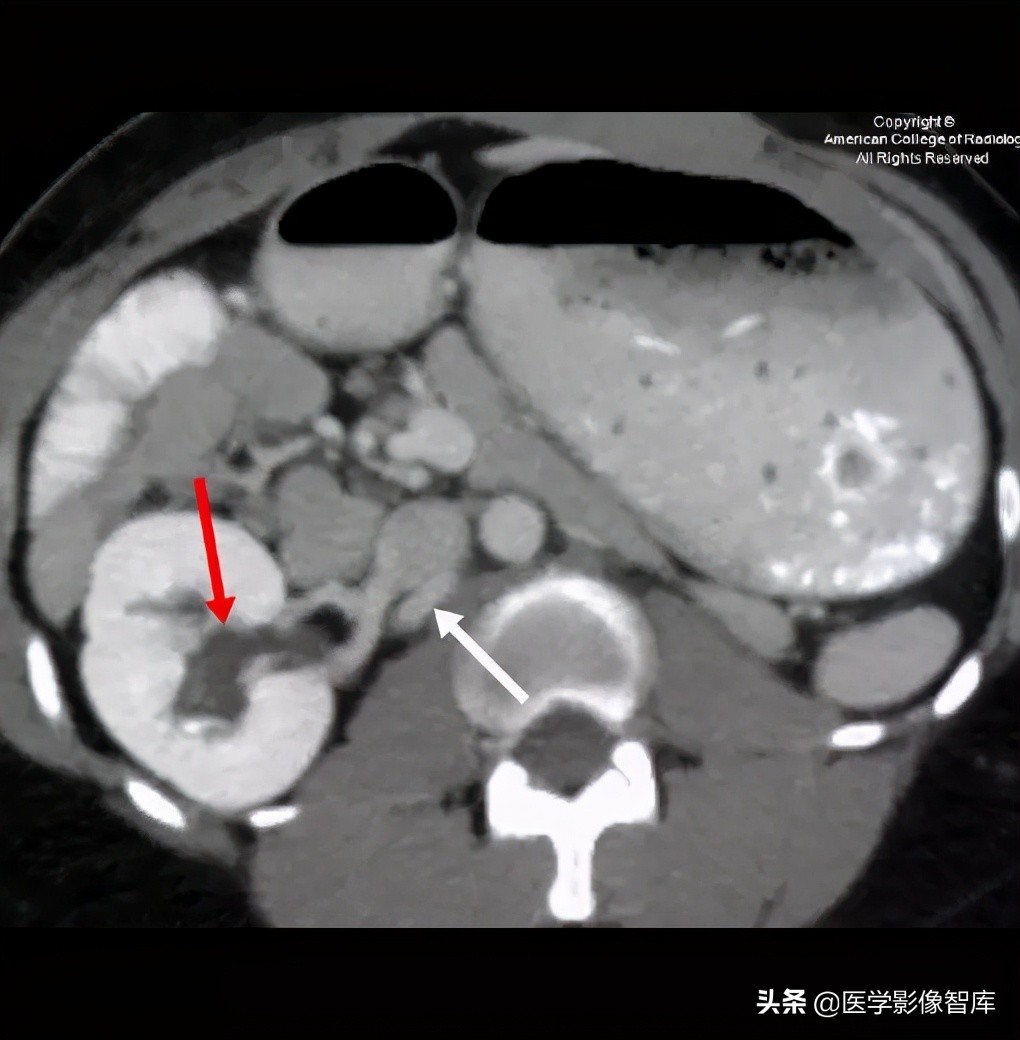

图 5. 轴位 CT 显示右肾肾盂扩张(红色箭头),右肾扩张,左肾发育异常,腔后右肾静脉(白色箭头)